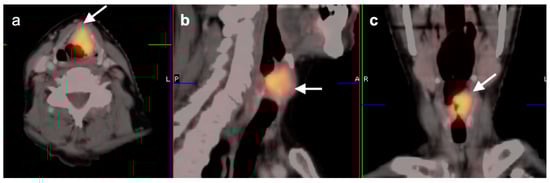

2.6. Thyroid Cancer

- Medullary thyroid cancer